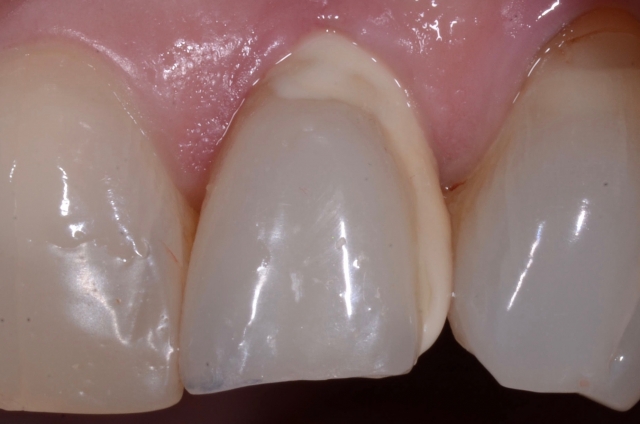

The story starts with a patient who had been referred to me for restoration of an implant in the position of #10. By the time the patient was referred to me, the implant was already in and the surgeon had done an immediate provisional, as you see here: